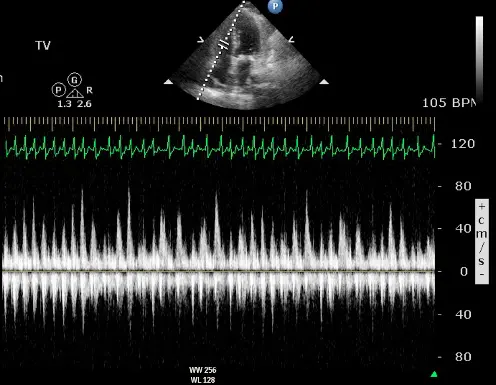

Echo

“Echo diagnosis of constriction is all about pattern recognition” - Sanjiv Shah

Ventricular Interdependence? Think constriction

Constrictive physiology should be considered when evidence of enhanced interdependence is observed by echocardiography.

- Diastolic septal bounce

- Ventricular interdepence and Respirophasic Variation

- Expiration: mitral inflows ↑, tricuspid inflows ↓

- “When you expire, you increase the pressures in the thorax, but that doesn’t transmit to the LV. And so you have an increased drive from the pulmonary veins to go into and fill the left side. And so in expiration, your mitral inflow goes up. But because of that ventricular interdependence, your tricuspid inflow goes down. And so you have this respirophasic variation in mitral inflow going up with expiration, tricuspid inflow going down with expiration, and then vice versa with inspiration. But for the same exact reason, you get respirophasic shifts in the septum. And so if you do an M-mode through the PLAX view, you’ll see the septum globally shifting towards the right side because the LV is filling during expiration and then shift back towards the left side because the RV is preferentially filling better during inspiration.”

- Mitral inflow ↑ respiratory variation, ↑ E/A, ↓ E deceleration time